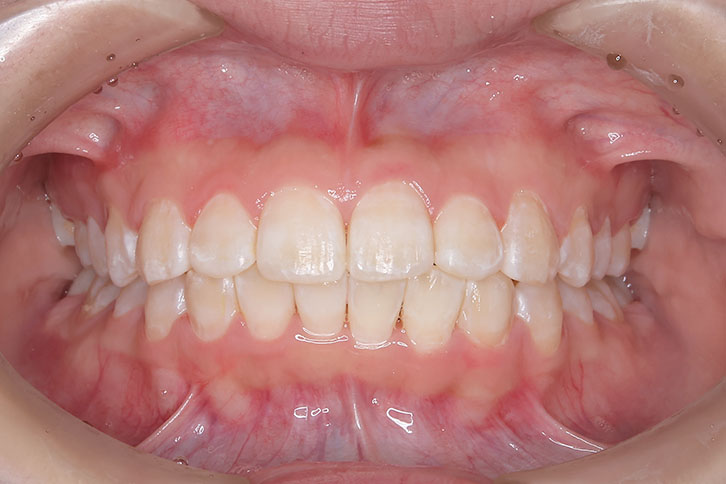

小児矯正での早期治療で、側方拡大による十分なスペース確保をしていたことと、口唇の前突傾向がなかったことから、